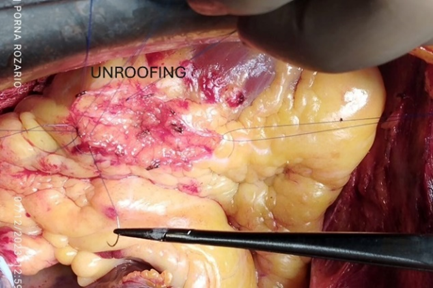

Then aorta was cross clamped and heart was arrested with antegrade cold-blood cardioplegia. After that to inspect epicardial surface of heart for intramyocardial LAD, was easily detected. Epicardial incision was given over the normal site of LAD coronary artery with 15 size surgical blade. Then dissection was extended proximally into the bridging portion of LAD coronary artery with the dissection of epicardial fat and underlying muscle or myocardial bridge with the help of Potts scissors and Electrocautery. The length of the myocardial bridge was about 4.5 cm. Careful dissection was done to avoid damage to the LAD coronary artery and its branches such as diagonal artery and to avoid injury to right ventricle. During dissection of epicardial fat and outer part of myocardial bridge electrocautery or Liga clip were used for hemostatic purpose.

Figure 9: Surgical Unroofing of Myocardial Bridge with exposed LAD artery.

Figure 10: Length of Myocardial Bridge.

To reduce and/or manage any bleeding (venous or muscular) from both sides of the myotomy edges, we employed over-and-over eversion sutures with 6/0 prolene, when patient was under cardiopulmonary bypass with full heparinization. The aortic cross clamp was removed. Proximal anastomosis was done on aorta with 6/0 prolene using side biting clamp. The patient was gradually weaned from cardiopulmonary bypass. After decannulation, heparin was reversed. After maintaining proper hemostasis, wound was closed in layers keeping two mediastinal drain tubes in situ. Patient was shifted to Cardiothoracic ICU with stable hemodynamic. He was extubated on 1st post-operative day and subsequent post-operative period was uneventful. Echocardiography was done on 1st post operative day showed preserved biventricular function. Patient was discharged from the hospital on the 7th day after surgery.